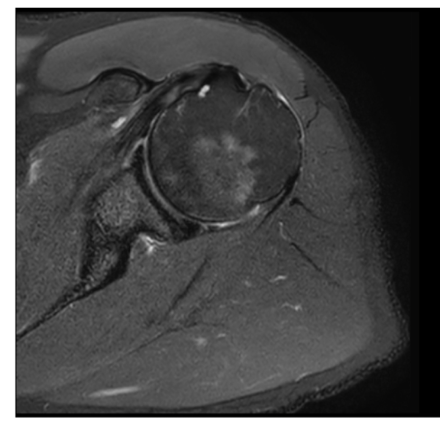

What is the sequence + pathology?

• T1 – fat is bright fluid is dark

• Path = avascular necrosis of the

femoral head

• Lost blood supply to the femoral

head. = bone death

• Decreased signal = oedema